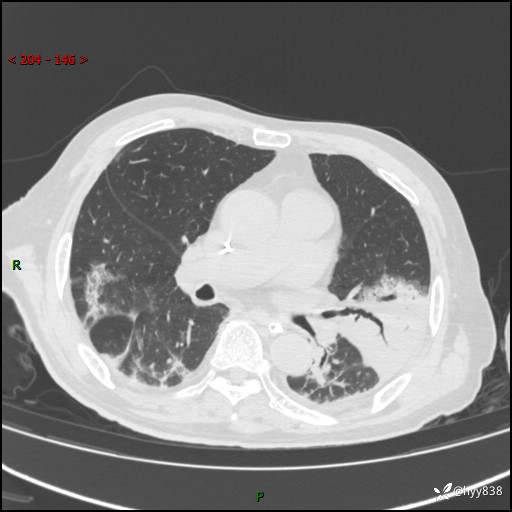

胸部CT复查(2024.8.5)